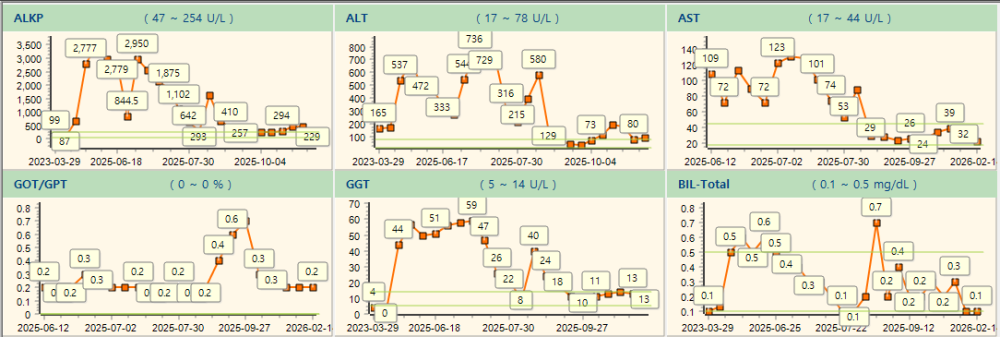

다음은 치료 결과에 따른 혈액검사 추이입니다.

간수치 모두, cPL(췌장염) 수치와 함께 같이 움직이는 것을 볼 수 있으며, 차차 개선세로 수렴하고 있는 모습입니다.